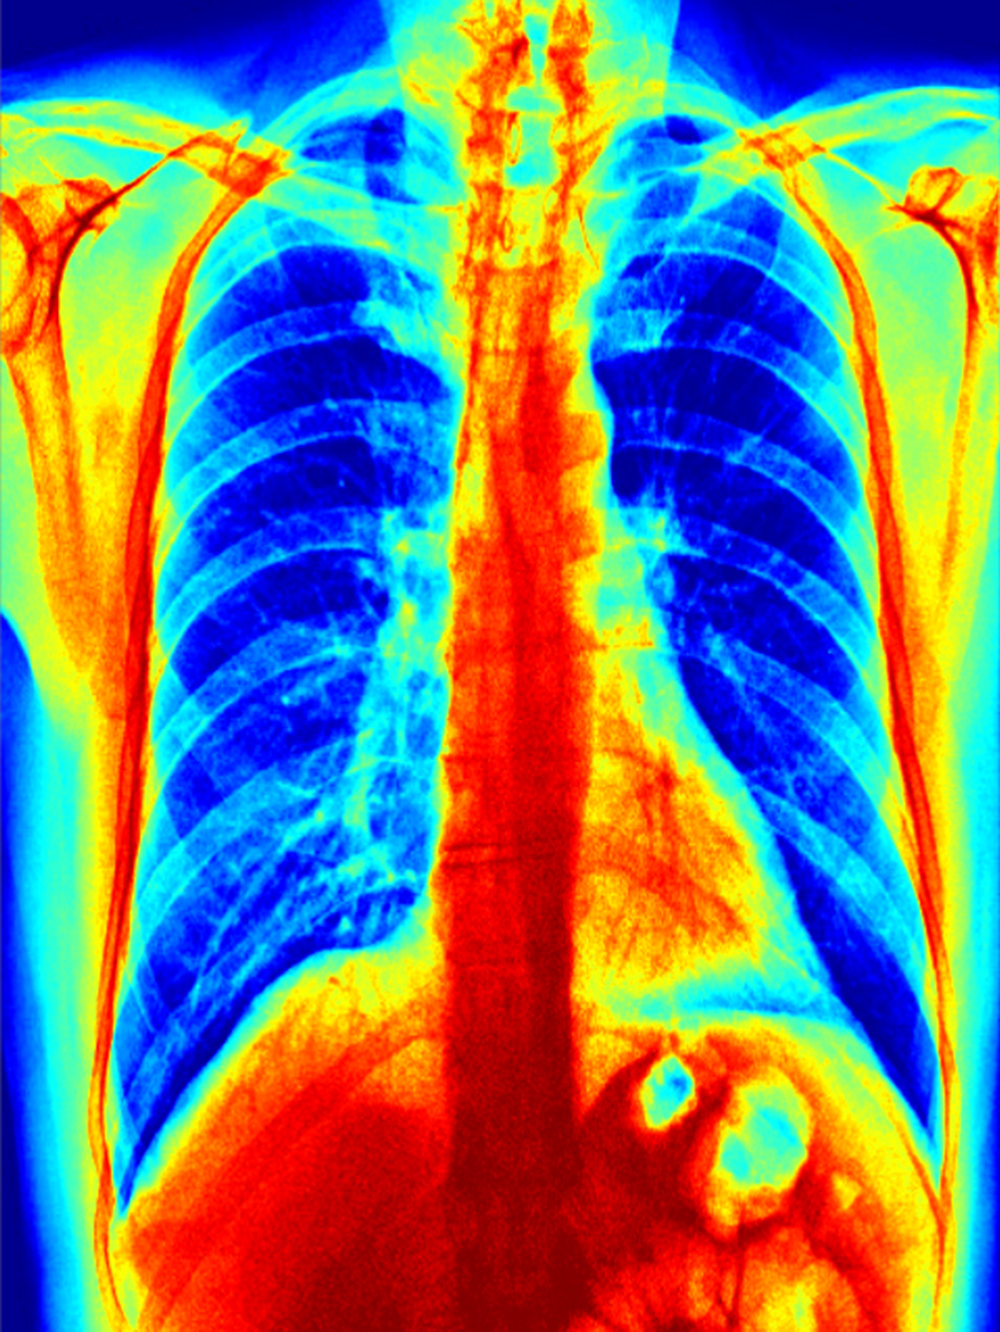

Zur automatisierten Auswertung werden die Aufnahmen in einen Standard-PC eingelesen und mit einer speziellen mathematischen Operation der Kontrast erhöht – ein Vorteil bei qualitativ schlechten Aufnahmen, die mit älteren Röntgenanlagen entstehen. Die Software erstellt neben einem Falschfarbenbild, das die Auswertung vereinfachen kann, ein Binärbild, auf welchem sich bereits die Umrisse der Lunge sowie Spuren von geschädigtem Gewebe erkennen lassen. Durch einen weiteren Algorithmus werden die im Binärbild vorhandenen Kanten und Grenzen der einzelnen Bereiche ermittelt. Die Software kann durch weitere Berechnungen Flächen- und Symmetriebetrachtungen vollziehen und anhand dieser mit großer Wahrscheinlichkeit zwischen bakterieller- oder viraler Lungenentzündungen unterscheiden.

Falschfarbendarstellung der Lunge. Foto: HHN